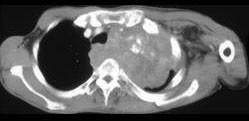

问题 男,68岁,咳嗽,胸痛,呼吸困难伴四肢无力半月余,请结合影像学检查,选出最可能的诊断 ( )

选项 A、纵隔畸胎瘤 B、恶性胸腺瘤 C、肺结核 D、淋巴瘤 E、肺癌

答案 B